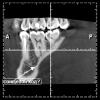

АнтонТЛТ Опубликовано 2 августа, 2012 Поделиться Опубликовано 2 августа, 2012 А вот ещё около 4 рядом с 5 чуть ниже какое то потемнение, это надеюсь не киста?Не киста, это ментальное отверстие место выхода сосудисто-нервного пучка из челюсти+1 к Bier, на одном из сканов похоже на ход от свища в обл 5. Навряд ли такие проявления от 8не похоже на свищ это скорее сосуды в кость входят, это же язычная сторонаhttp://i026.radikal.ru/1208/8d/08cbf45a53e4.jpgТам еще есть такие входыhttp://s017.radikal.ru/i433/1208/2e/fbe2e4941db9.jpg Ссылка на комментарий

АнтонТЛТ Опубликовано 2 августа, 2012 Поделиться Опубликовано 2 августа, 2012 Есть глубокий карман в области 6 зубаhttp://s42.radikal.ru/i098/1208/59/02cafd214a21.jpgИ глубокая кариозная полость в 7 зубеhttp://s40.radikal.ru/i087/1208/e9/76f66a060093.jpg Ссылка на комментарий

K_gur Опубликовано 9 сентября, 2012 Поделиться Опубликовано 9 сентября, 2012 Спасибо kriokov !Ещё я не пойму откуда у меня Свищ...5 зуб мне запломбировали основательно до конца...вобще зачем мне его плобировали непойму до сих пор..Может когда очищали каналы и пломбировали ..что то пошло вниз, а далее из корня в десну?Зубы так не болят....ничего не шатаеться....что за беда?(. Что теперь мне будет снова 5 зуб сверлить??? Очищать пломбу....? А ведь здоровый зуб! был....Свищ может идти просто от надкосницы из шеки? Не от зуба?А вот ещё около 4 рядом с 5 чуть ниже какое то потемнение, это надеюсь не киста? http://img12.imageshack.us/img12/2126/42903832.jpgто что вы обвели красным!!!!!!!!!!!!! у этой программки насколько я вижу есть настройка срезов которую вы не поправили, эта панорамная линия по альвеоле должна идти. а то получилось что форамен менталес, как это подбородочная форамен не знаю как по русский сидит на апексе зуба Ссылка на комментарий

K_gur Опубликовано 9 сентября, 2012 Поделиться Опубликовано 9 сентября, 2012 теперь во вторых по вашим снимкам насколько можно судить и по рассказу, у вас всё началось с перикоронарита, резали резали и в конце концов по косой линии экссудат пошло в период и открылся свищ у 5 го, тут я думаю надо обследовать 8 зуб и при надобности а я думаю что таковая есть надо удалять.я тут вспомнил пациента которого лечили от туберкулеза, свищ на ключице, Манту положительное видите ли,, Манту у меня тоже положительное, оказался 46 зуб, когда ввели контраст пошло прямо к нему Ссылка на комментарий